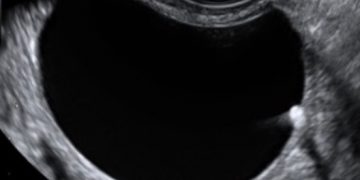

Guida al Counselling di Ottobre 2022: ridotta riserva ovarica e CFA

Cari colleghi, vi presentiamo la guida al counseling di Ottobre relativa alla ridotta riserva ovarica e alla conta dei follicoli antrali!! Potrete scaricarla cliccando sul link. Grazie a Carlotta Zorzi...